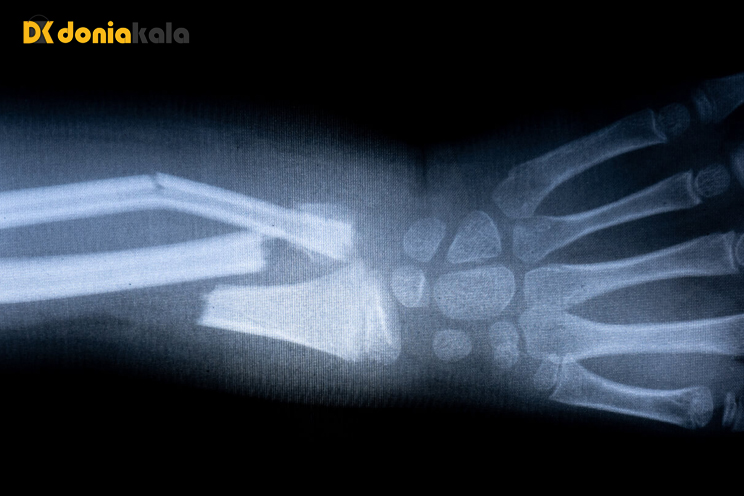

شکستگی شکستگی جزئی یا کامل در استخوان است. هنگامی که یک شکستگی اتفاق می افتد، به دو دسته باز یا بسته طبقه بندی می شود/ انواع شکستگی:

شکستگی باز (شکستگی مرکب): استخوان از پوست عبور می کند و قابل مشاهده است. یا یک زخم عمیق استخوان را از طریق پوست نمایان می کند.

شکستگی بسته (شکستگی ساده): استخوان شکسته است، اما پوست سالم است.

اشعه ایکس: یک آزمایش تشخیصی که از پرتوهای انرژی الکترومغناطیسی نامرئی برای ایجاد تصاویری از بافتها، استخوانها و اندامهای داخلی روی فیلم استفاده میکند.